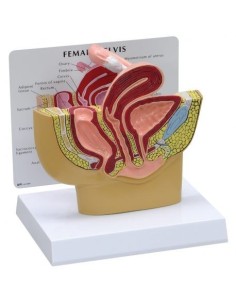

3B Modèle scientifique et gynécologique pour l'entretien avec les patientes P53

3B Scientific. Kit d'enseignement, système de reproduction femelle W40214

3B Modèle anatomique scientifique du bassin gravide, décomposable en 3 parties L20

Pelvis masculin 3B Scientifique avec ligaments, vaisseaux, nerfs, plancher pelvien et...

Modèle anatomique du squelette du bassin d'un homme 3B Scientific H21/1

3B Bassin scientifique, anatomique Modèle pour illustrer l'accouchement L30